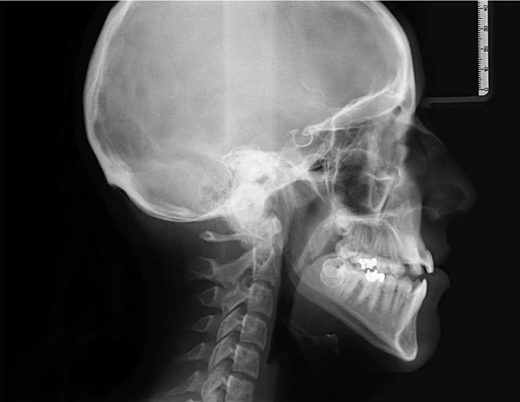

The cephalogram is an x-ray of the skull and jaws. It is mainly used in orthodontics to evaluate bone growth and teeth development.